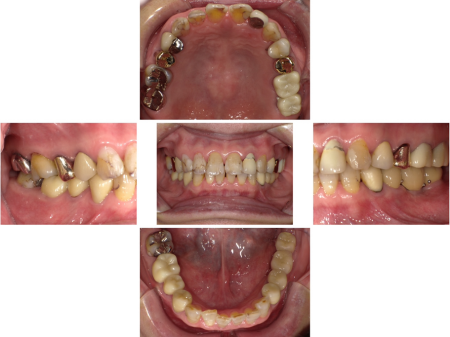

「噛み合わせが悪く、口の中を噛んでしまって繰り返し口内炎ができる」とご相談いただきました。当院の噛み合わせ治療を受けたご友人からの紹介で、2015年より遠方から来院されている患者様です。

拝見したところ、初診時から適合が悪い被せ物や詰め物がお口の中に多数あり、噛み合わせを整えるため当院にて、被せ物治療や人工歯根を利用した「インプラント治療」を実施しています。

噛み合わせ治療を進めていく中で、噛んだ時に下の前歯が上の前歯に強く当たり 、上の前歯6本(右犬歯/3番〜左犬歯)が外側に傾いていることを確認しました。

さらに上の前歯はプラスチック樹脂の「コンポジットレジン」でところどころ修復した履歴があり、左上前歯(側切歯/2番)には被せ物が装着されています。これらは、下の前歯が上の前歯を突き上げることによってダメージを受けたことが原因で治療に至ったと推測しました。

このままだと噛むたびに上下の前歯がダメージを受け、再び治療が必要になる可能性があります。また、歯が傾いていることで口の中の粘膜を噛みやすく、日頃から口内炎が度々できることにも負担を感じていらしたため、上前歯の傾きなどを改善する必要があると診断しました。

前歯の噛み合わせと歯の傾きを改善するため、上の前歯6本に被せ物を装着する治療を提案し、同意いただきました。

上の前歯は人目につきやすく見た目が気になる部分でもあるため、患者様と相談の上、被せ物の材質は強度と自然な美しさが特徴の「フルジルコニア」に決定しました。